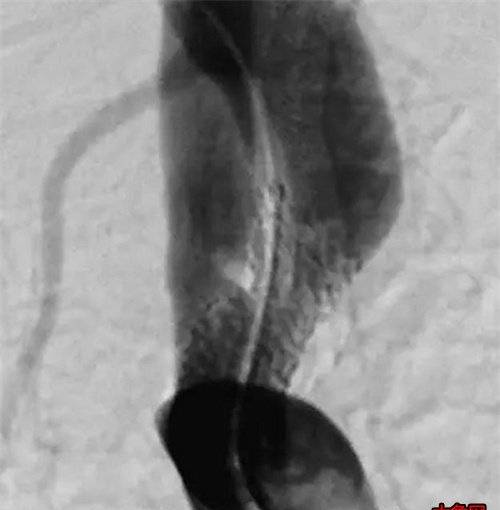

球囊缓慢扩张

支架完全释放,盗血症状改善

经过三位医师的通力合作,密切配合,董老在30分钟内完成血管内介入治疗,再测双上肢血压,发现右侧血压BP:125/65mmHg,左侧上肢血压:134/70mmHg。双上肢的血压脉压差相差不到20mmHg,基本达到治愈。